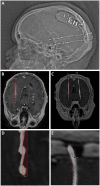

Background: Robotic stereotaxy is increasingly common in epilepsy surgery for the implantation of stereo-electroencephalography (sEEG) electrodes for intracranial seizure monitoring. The use of robots is also gaining popularity for permanent stereotactic lead implantation applications such as in deep brain stimulation and responsive neurostimulation (RNS) procedures. Objective: We describe the evolution of our robotic stereotactic implantation technique for placement of occipital-approach hippocampal RNS depth leads. Methods: We performed a retrospective review of 10 consecutive patients who underwent robotic RNS hippocampal depth electrode implantation. Accuracy of depth lead implantation was measured by registering intraoperative post-implantation fluoroscopic CT images and post-operative CT scans with the stereotactic plan to measure implantation accuracy. Seizure data were also collected from the RNS devices and analyzed to obtain initial seizure control outcome estimates. Results: Ten patients underwent occipital-approach hippocampal RNS depth electrode placement for medically refractory epilepsy. A total of 18 depth electrodes were included in the analysis. Six patients (10 electrodes) were implanted in the supine position, with mean target radial error of 1.9 ± 0.9 mm (mean ± SD). Four patients (8 electrodes) were implanted in the prone position, with mean radial error of 0.8 ± 0.3 mm. The radial error was significantly smaller when electrodes were implanted in the prone position compared to the supine position (p = 0.002). Early results (median follow-up time 7.4 months) demonstrate mean seizure frequency reduction of 26% (n = 8), with 37.5% achieving ≥50% reduction in seizure frequency as measured by RNS long episode counts. Conclusion: Prone positioning for robotic implantation of occipital-approach hippocampal RNS depth electrodes led to lower radial target error compared to supine positioning. The robotic platform offers a number of workflow advantages over traditional frame-based approaches, including parallel rather than serial operation in a bilateral case, decreased concern regarding human error in setting frame coordinates, and surgeon comfort.